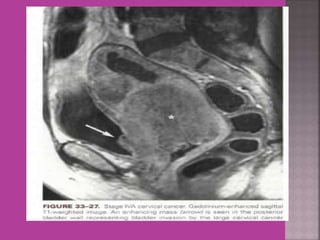

 Gynaecological cancers--- 1. Cervical cancer –extent of parametrium and pelvic organs , pelvic L.N., Endocervical. 2.Endometrial cancer –Myometrial invasion, downward extension to cervix. 3. ovarian cancer—malignant versus benign mass, ascites , retroperitoneal node > 1cm , Bowel bladder , ano rectal . Parietal peritoneum , liver and or omental metastasis. 4. Pregnancy --- complicated by genital cancers

Ca CX – Extending to Bladder Uterus